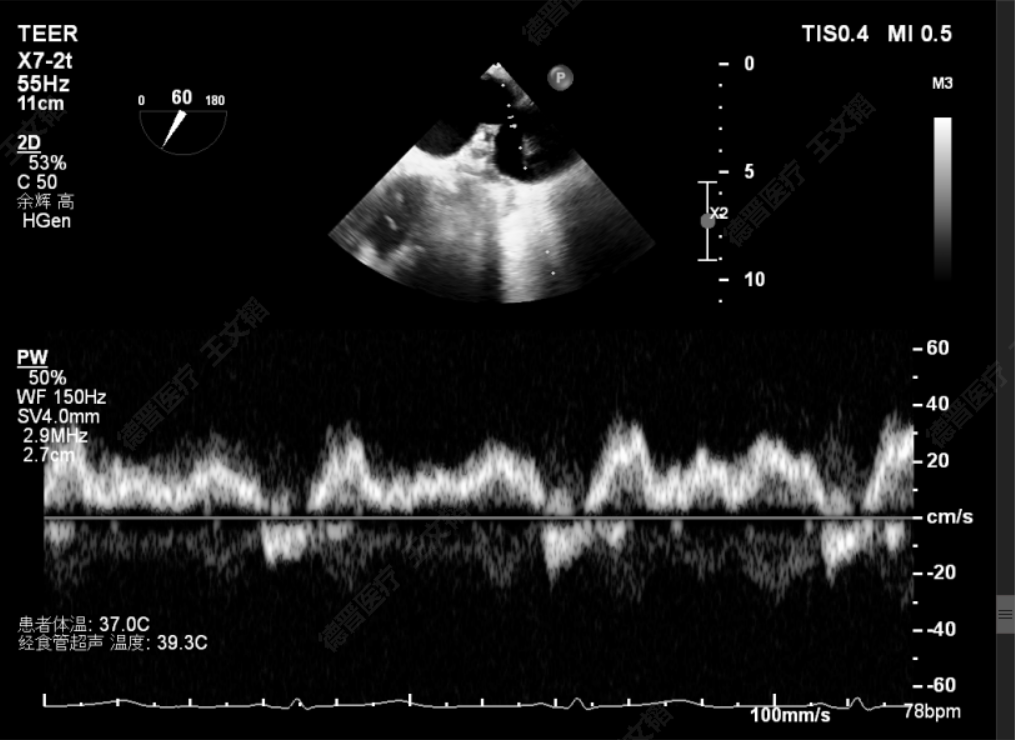

术前静脉逆流

术后静脉逆流

术前潘宏伟教授、何晋教授团队讨论决定,先于2偏1区置入一枚长宽(XW0612)夹解决最大的一处脱垂,再依次向内侧补夹子。术中房间隔穿刺高度:4.4cm,于2偏1区植入一枚长宽(XW0612)夹,夹闭后L侧无残余脱垂。再于M侧2区Side by side植入一枚长宽(XW0612)夹,夹闭后第一枚夹子较前稳定,M侧有残余脱垂。最后于M侧2偏3区植入一枚长窄(XN0412)夹,夹闭后残余功能性反流Trace,压差5mmHg,术毕,反流即刻由术前重度降低为Trace,左房压由术前45mmHg降至术后22mmHg,肺静脉逆流几乎消失,患者明显获益。